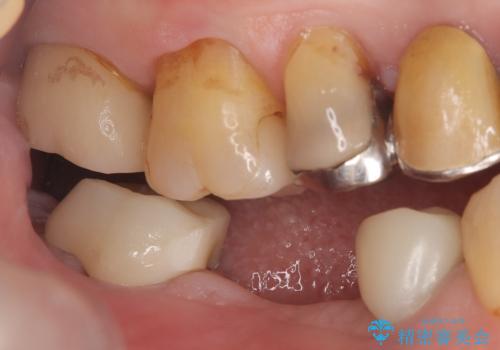

- 主訴:つい先日入れたセラミック(ジルコニア)ブリッジが奥歯部分で割れた。いつも同じ場所で壊れる。これで3度目。

セラミックに比べ、割れづらい金属(ゴールドでのブリッジのやり替えとなりました。

セラミックに比べ、破折リスクの少ない金属を使用したブリッジでのやり替えとなりました。

両支台歯が失活歯のため、どちらかもしくは両方の歯が破折した際、再度ブリッジを除去した治療が必要になるリスクとインプラント治療のご提案もさせていただきましたが、ブリッジでの治療を希望されました。

右下5番は支台歯CR築造を行っています。